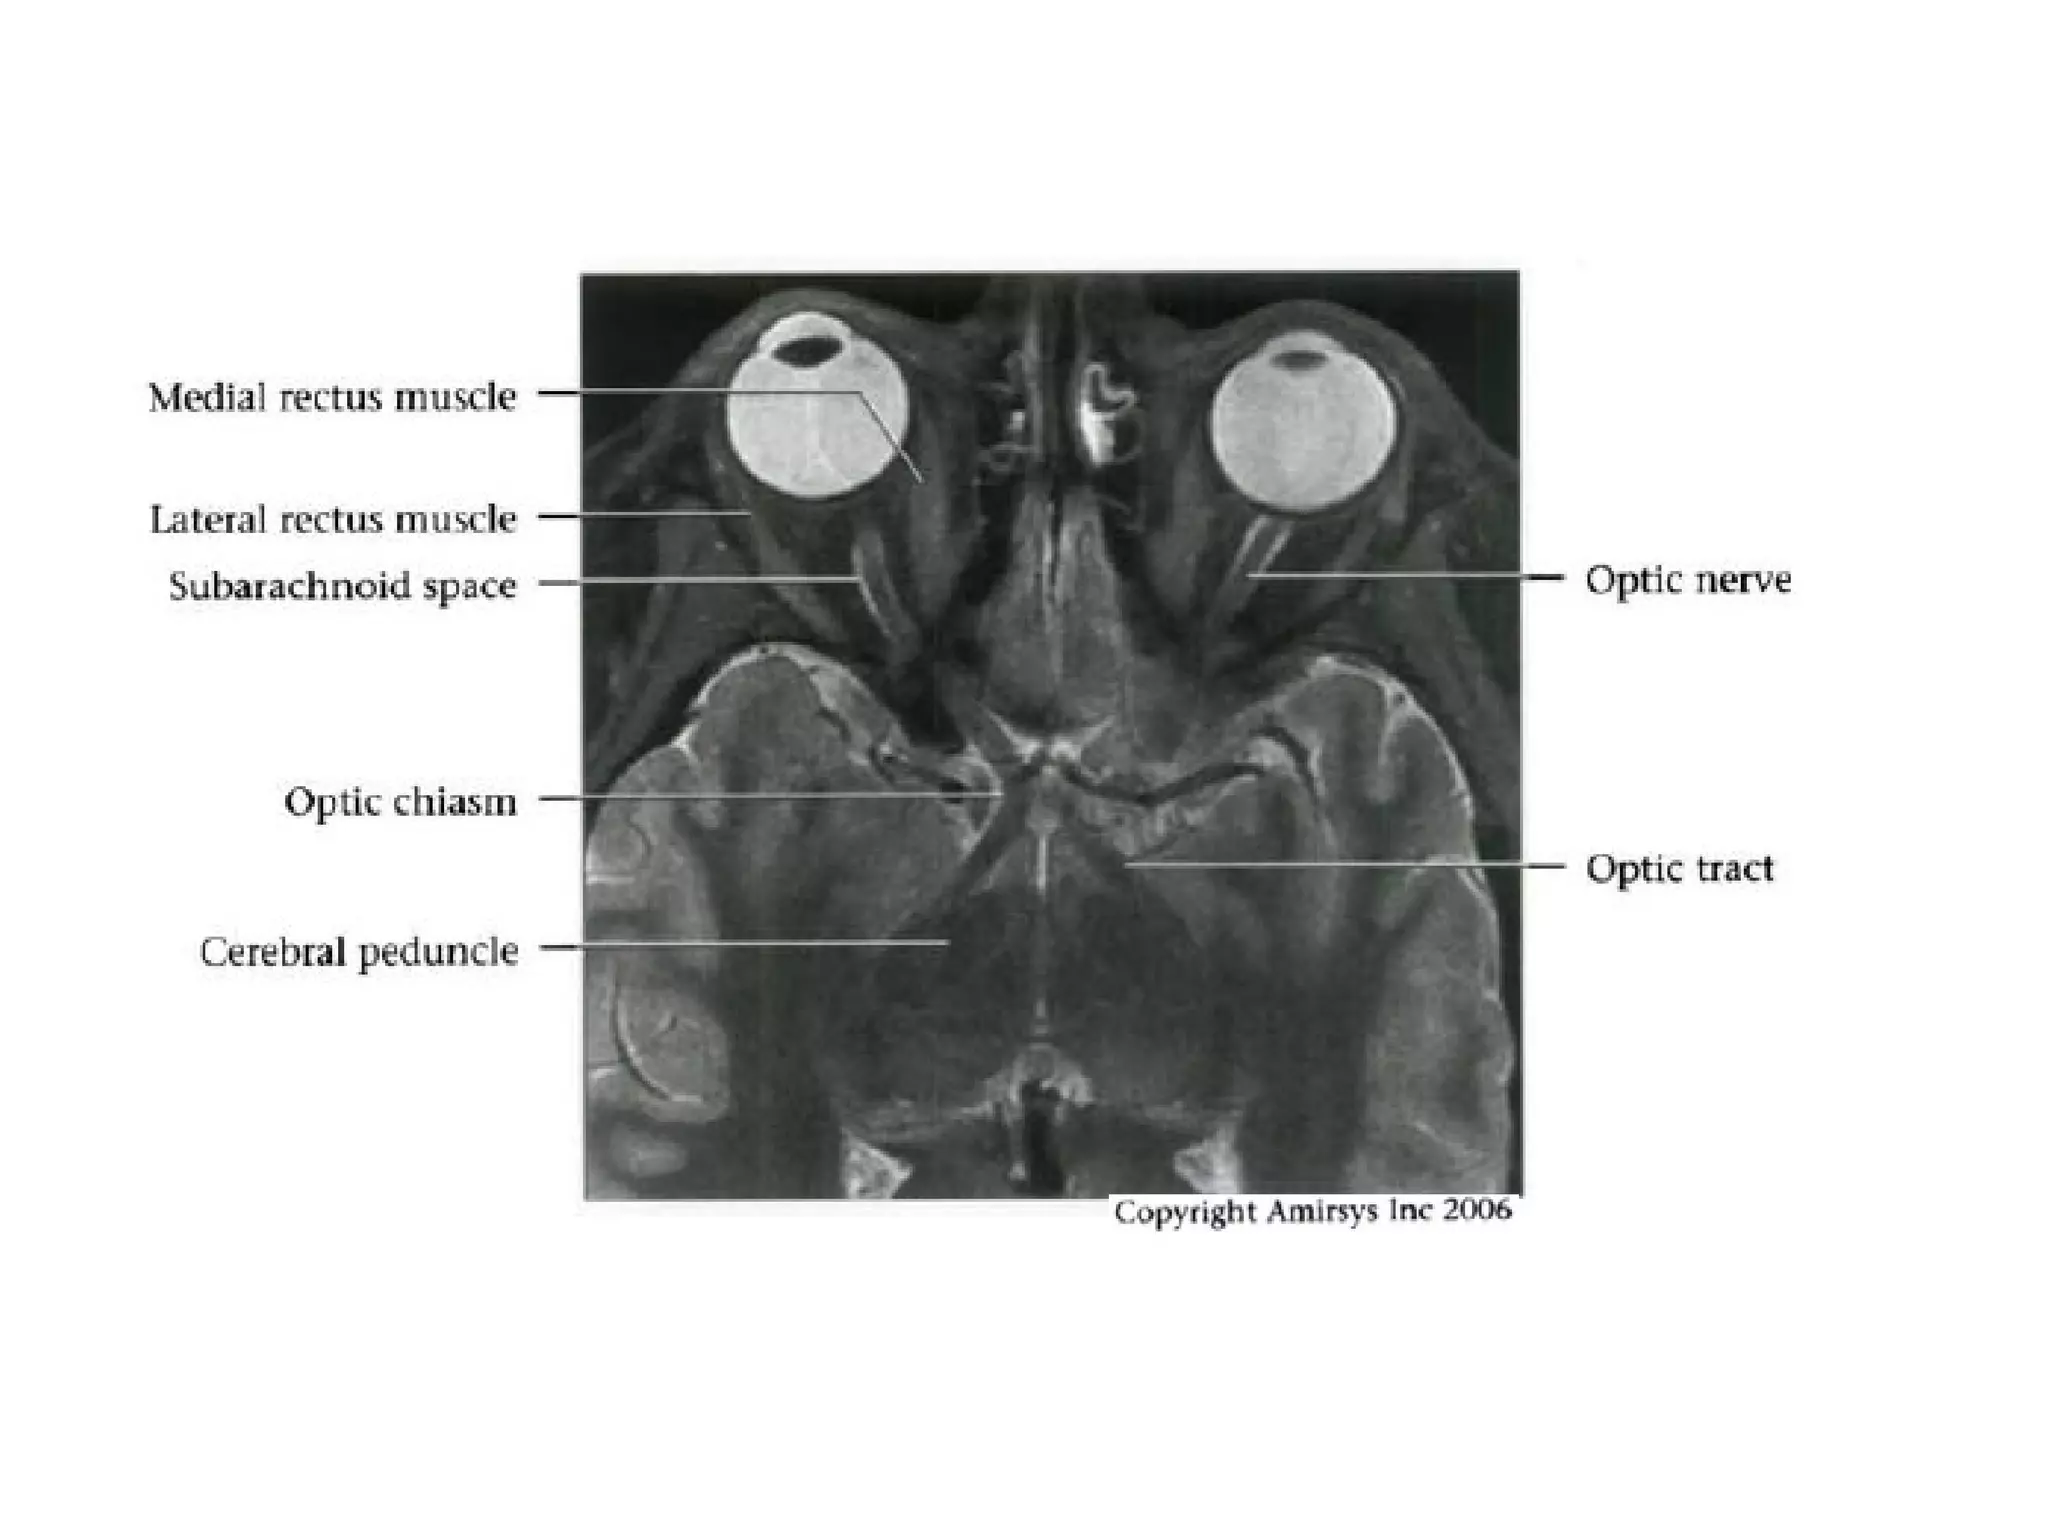

Optic nerve.

Axial oblique 0.8-mm-thick SSFP MR image shows three of four segments of the optic

nerve: the retinal (black arrow), orbital (black arrowheads), and canalicular (white

arrowhead) segments. The infundibulum of the pituitary gland (white arrow) also is

seen. The fourth (cisternal) segment of the optic nerve would be visible on more

superior images.

The cisternal segment of the optic nerve (white arrow) leads to the chiasm, which

resembles the Greek letter χ in this plane. The optic tract (white arrowheads) leads

backward from the chiasm to the thalamus. Important anatomic landmarks include the

mamillary bodies (black arrowhead) and the anterior cerebral artery (black arrow).

RadioGraphics 2009; 29:1045–1055